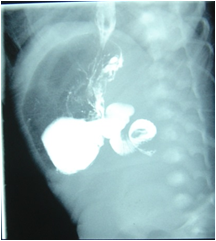

上消化道钡餐

腹部直立前后位平片:双泡征(左上腹和右上腹略低处),下腹部有少量气泡影

钡剂灌肠:盲肠和升结肠位于上腹部或左侧

腹部GI:十二指肠框分布异常,小肠集中于右侧腹部